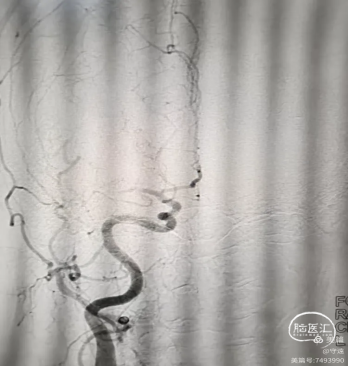

3.取栓8F指引导管置于C1段,中天远端通路导管裸奔至M1段,导管尾部连接延长管,5OmL注射器"踹马桶"抽吸,无回血,负压下撤出体外,检查结果见约0.5cm大小白色血栓和少量点片状红色血栓。

4、快速二次接续抽吸:清理可能的残余血栓后造影右侧大脑中动脉血流通畅,未见明确血栓逃逸和狭窄。结束手术。

术后情况:意识清楚,言语流利,左侧下肢肌力3级,上肢肌力1级。

术后管理:床头摇高30度,给予依达拉奉佑茨醇、甘露醇脑保护,替罗非班泵入。甲强龙120mg连用3天。

术后2小时左下肢肌力3级+,左上肢肌力1级,言语清晰,伸舌正常,双眼凝视消失。术后3小时给予替罗非班维持量6mL/h泵入24小时。

术后24小时复查CT,无明显水肿,中线无偏移,右侧內囊小片状出血性梗塞,左侧顶枕小片状出血。点状出血原因:考虑为豆纹动脉为终末血管,再通出血,或替罗非班的原因。

查CT,右侧内囊小片状低密度影,出血吸引消失。